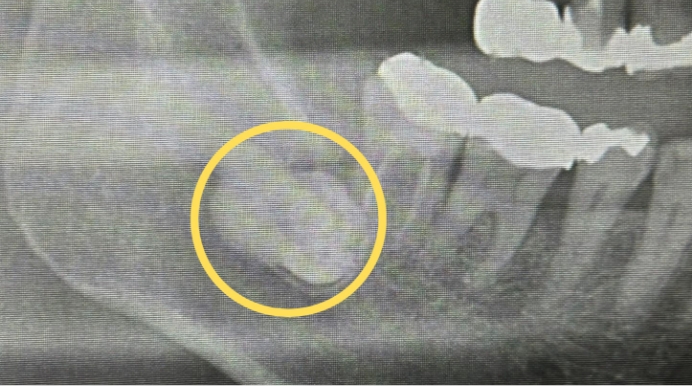

左下の親知らずを抜きたい

- 親知らずの生え方

- 横になって骨の中に埋まっている

- 抜歯時間

- 約30分

- 抜歯費用

- 約8,000円